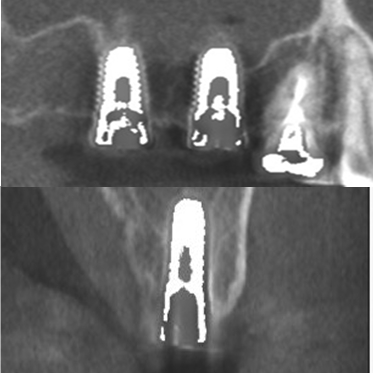

● 上の顎の奥歯にインプラントを入れるのに骨が足りないため、ソケットリフトと人工骨補填して骨造成を行った症例1

術前

藤沢デンタルオフィスのインプラント術前 藤沢デンタルオフィスのインプラント術前

3Dシミュレーション

術後

藤沢デンタルオフィスのインプラント術後 藤沢デンタルオフィスのインプラント術後

シミュレーション通りの上顎洞底挙上と人工骨補填(3Dガイドシステム使用)